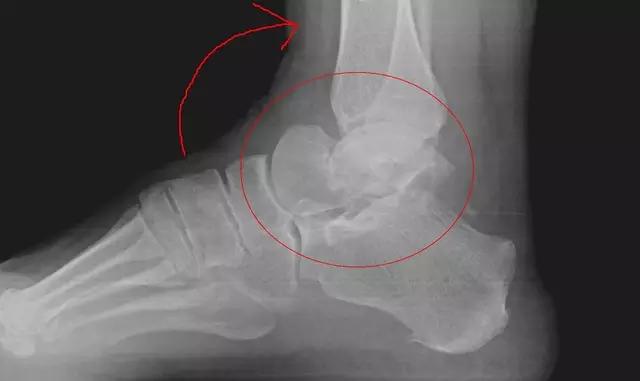

11. Shepherd 骨折

距骨后结节的骨折。

(来源:Talar process or tubercle [Shepherd’s fracture)